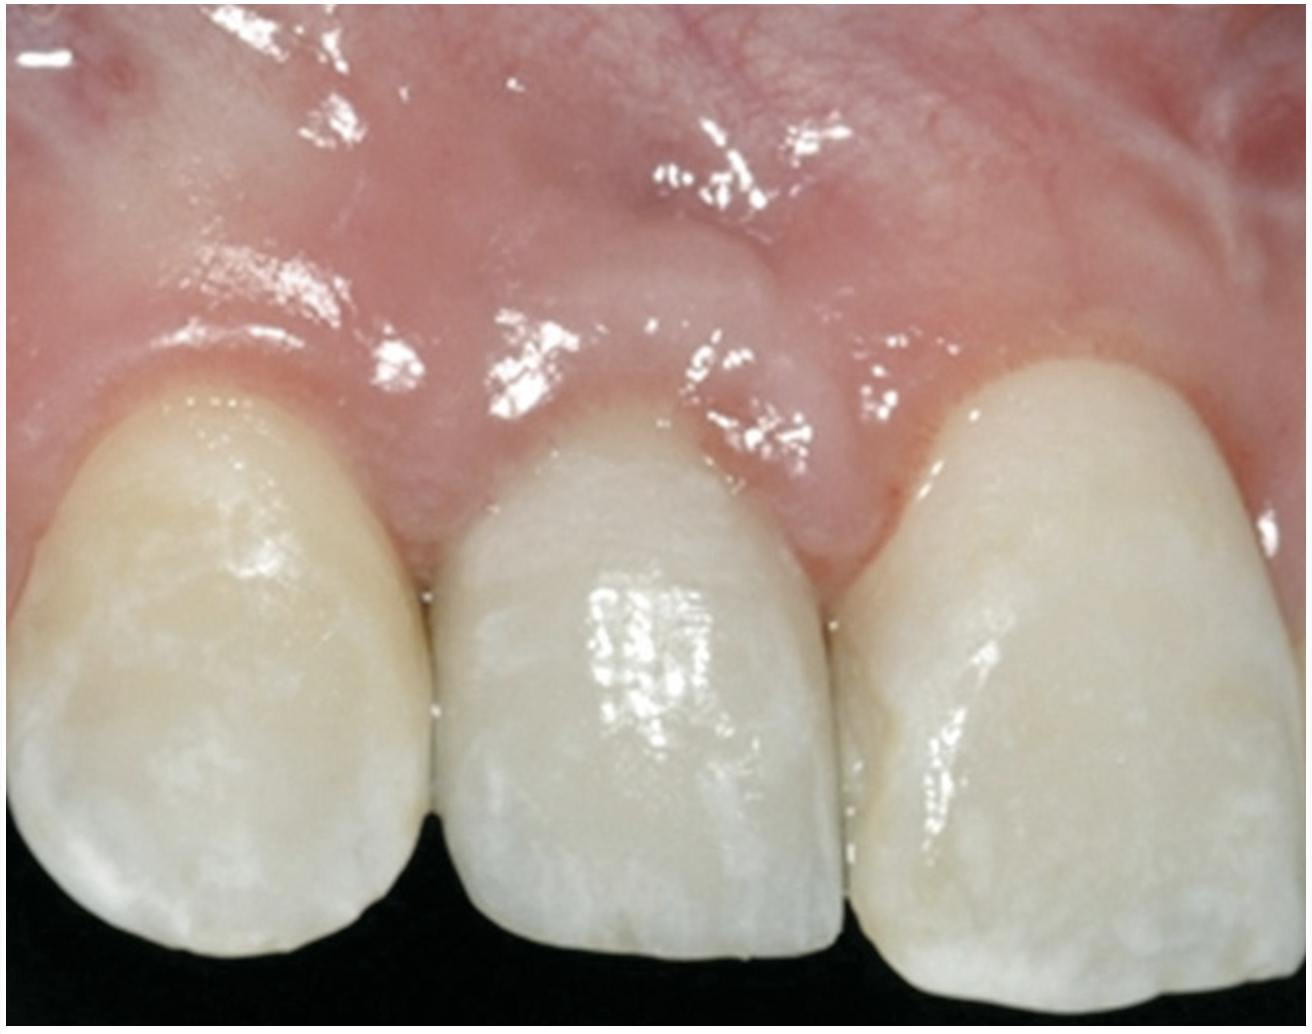

Figure 2  Congenitally missing maxillary right lateral incisor.

Figure 2

Case 1

A 16-year-old female patient with a congenitally missing maxillary right lateral incisor was referred for an implant-supported crown. Clinical and CBCT evaluation revealed both a facial and palatal bony width deficiency (Figure 2 and Figure 3). The treatment plan included the use of titanium mesh and rhBMP-2/ACS (INFUSE® Bone Graft) along with mineralized allograft (MinerOss®, BioHorizons, www.BioHorizons.com) for bony augmentation (Figure 4 and Figure 5). After 7 months, the graft was found to be well incorporated and allowed for placement of a 3.8-mm x 10.5-mm diameter root form implant that was restored 3 months later (Figure 6, Figure 7, Figure 8, Figure 9 and Figure 10).